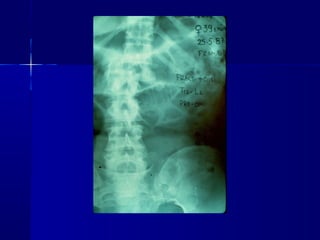

OPEN REDUCTION AND INTERNAL FIXATION

MISCELLANEOUS CASES

CASE 4

OPEN REDUCTION ANDINTERNAL FIXATION

• 196.